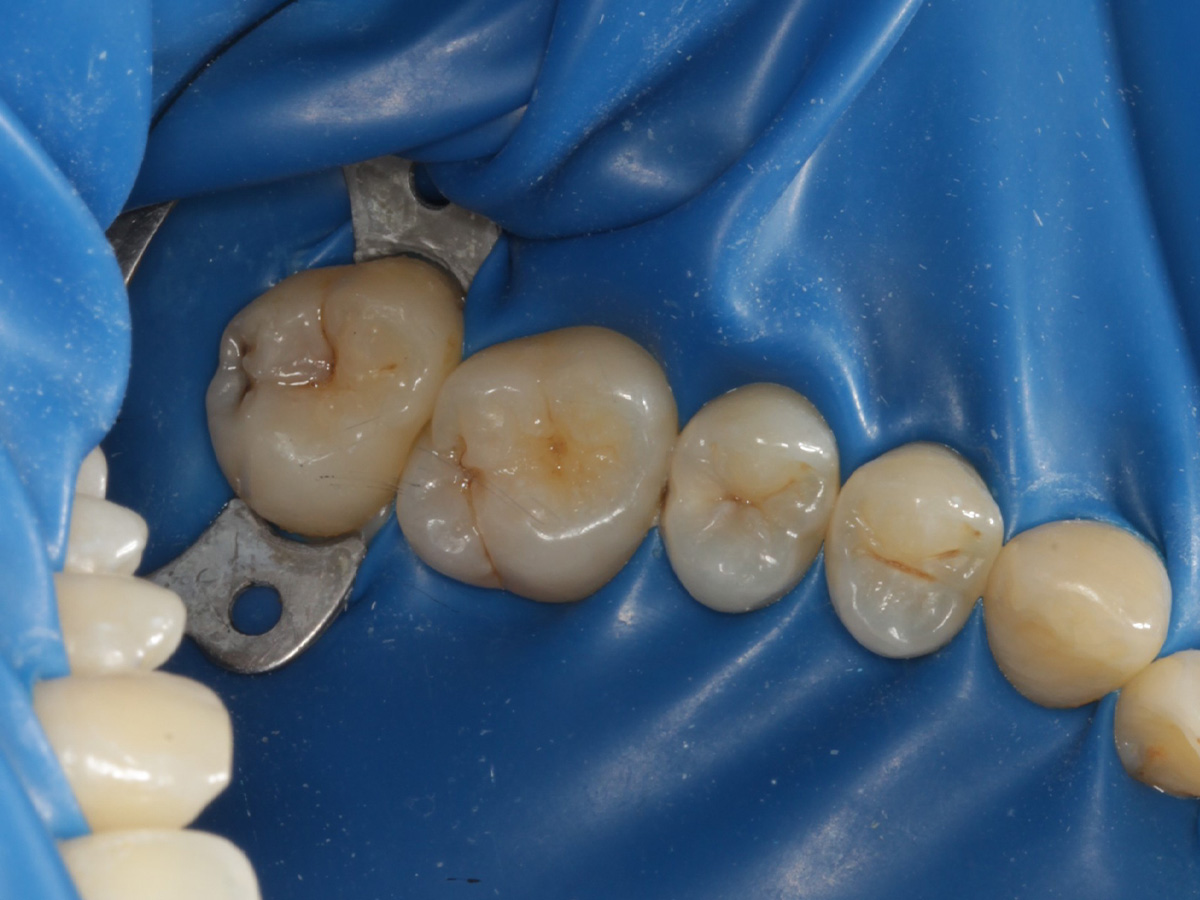

Abbildung 3

Quadrantenisolierung mit Kofferdam (x-heavy)